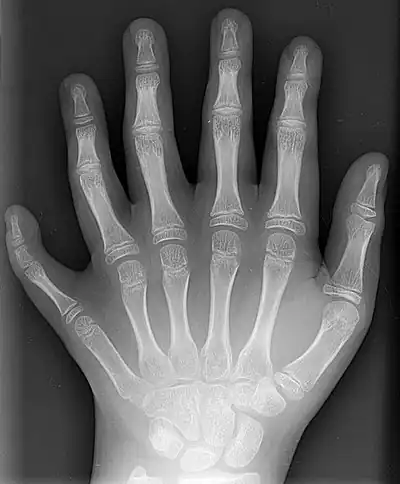

Radiogram of a polydactyl left hand.

Humans normally have five digits on each extremity. Each digit is formed by several bones called phalanges, surrounded by soft tissue. Human fingers normally have a nail at the distal phalanx. The phenomenon of polydactyly occurs when extra digits are present; fewer digits than normal are also possible, for instance in ectrodactyly. Whether such a mutation can be surgically corrected, and whether such correction is indicated, is case-dependent.[1] For instance the former chess world champion Mikhail Tal lived all his life with only three right-hand fingers.